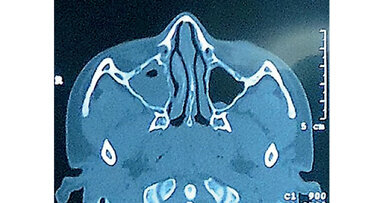

Examen radiográfico

La radiografía indica translucidez en el sentido vestíbulo-palatino del reborde residual y presencia de pneumatización de los senos maxilares, lo cual es una contraindicacción para la colocación de implantes dentales (Foto 2).